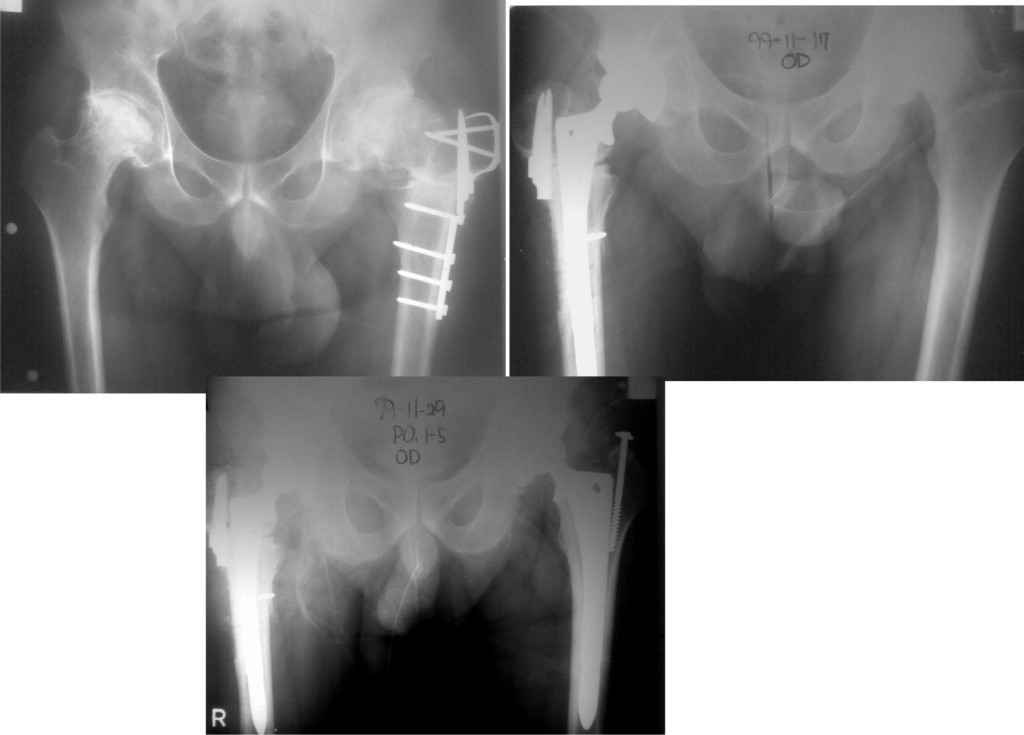

Уважаемый Станислав!

У меня опыт по эндопротезированию совсем небольшой. Еще 5 лет тому назад у нас в городе не было протезирования. Во вложении снимки одного больного из нашего города. который оперировался в 1999 году в Южной Корее. разница по времени замены второго сустава 11 дней. Больной по настоящее время ходит без проблем, особых жалоб не предъявляет, весит он 98 кг. Может быть есть смысл подождать, по наблюдать а оперировать никогда не поздно.

Удачи Вам!

К сожалению на снимках чашки просматриваются плохо. Вопрос: слева в бол. вертеле винт(на снимках после ТЭП). Это доступ с отсечением или что?

дело в том,что на снимках после замены второго сустава прослеживается ход дренажной трубки, т.е снимок контрольный сразу же после операции. Если этот доступ был с отсечением большого вертела, то не прослеживается линия остеотомии. По началу я тоже так и подумал, я считаю, что винт выполняет роль клина для стабильности ножки. Что касается качества снимков то согласен, но судя по контурам вертлужного компонента он напоминает ваш снимок.